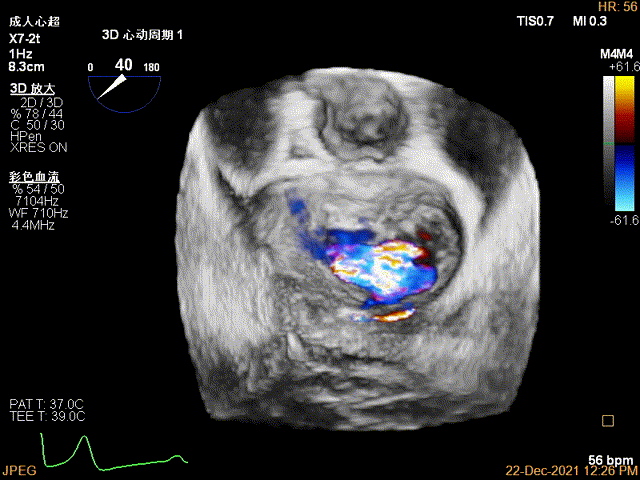

3D-color MV view:大量反流,起源于2区

Color-view:极大量反流,主要来源于2区